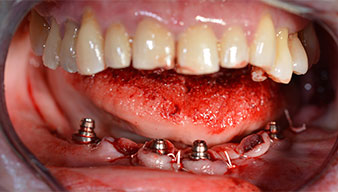

The 64-year-old patient presented with residual dentition of teeth 38, 33 and 43 and a clasp denture in the mandible (Fig. 1 and 2).

After removal of the residual dentition in the mandible, the alveolar crest was exposed from 37 to 47.

The mental foramen was first identified as a limiting anatomical structure and then the cortical bone of the crest was smoothed with the straight handpiece and a large rose-head bur (Fig. 4).